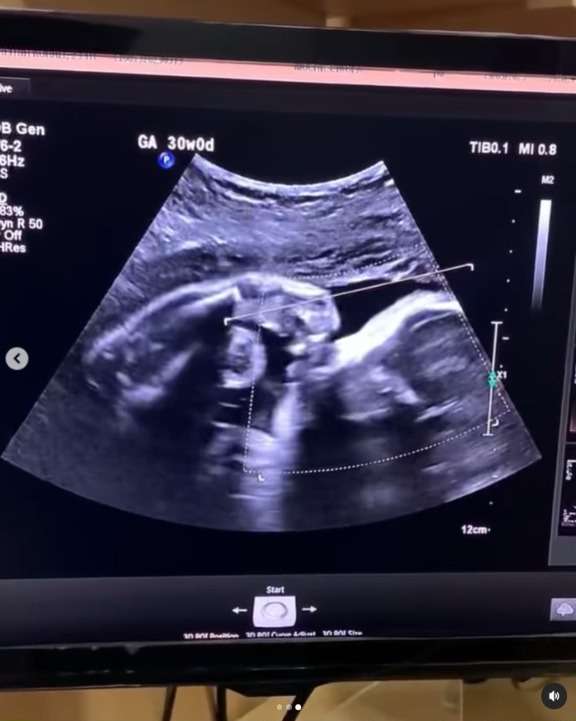

Ia mengatakan bahwa hatinya merasa bahagia saat melihat anak yang dikandungnya dalam keadaan sehat. Bahkan sang anak terlihat bergerak aktif saat menjalani USG.

“ Aku seneng banget pas usg bayiku gerak-gerak,” tulis calon ibu tersebut.

Namun, kesedihan itu langsung sirna berubah menjadi bahagia saat ia periksa usg dan melihat anak di dalam kandungannya menggerakkan tangan seperti sedang dadah ke ibunya.

Seolah bayi itu ingin memberitahu bahwa keadaannya di dalam baik-baik saja, sehingga sang ibu tidak perlu sedih dan khawatir lagi. Saking bahagianya, wanita ini sampai menangis saat melihat usg anaknya.